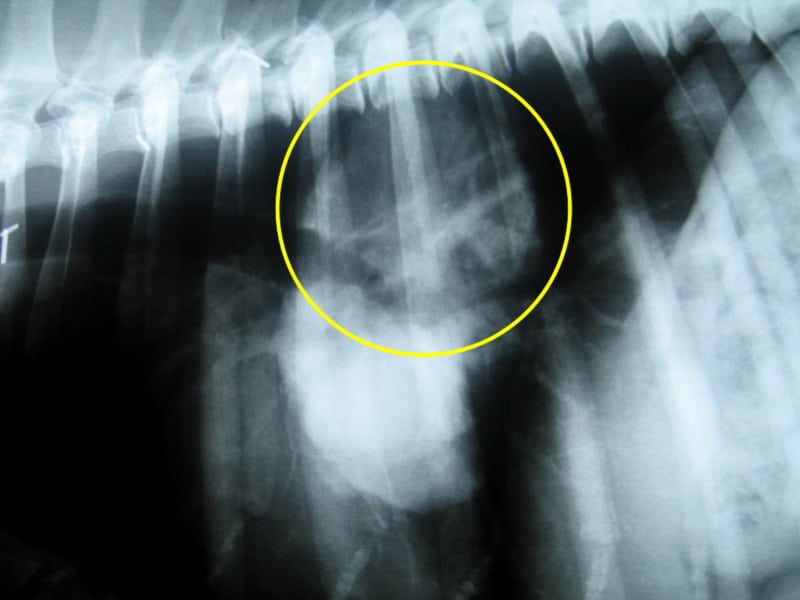

Tomorrow we’ll get the results from tests on blood and urine samples they took from me. But the films clearly indicate that I do indeed have a lump in my lung. More of a mass really, about the size of a softball from the looks of things. But as I have proven all along, I’m a special case.

osteosarcoma metastasis xrayUsually, osteosarcoma metastasis presents itself as multiple legions throughout the lungs. The doctor expected to see a “snowstorm” on the x-rays. And I could tell my people did too, deep down inside. Instead, I appear to have a single large growth, which may or may not be operable.

• osteosarcoma metastasis xrayAre they doing everything they can for me? (As if … I wouldn’t still be here if they haven’t done everything they have already!)

• Should they pay for the costly CT scan which that doctor would surely need to make any sort of accurate recommendations? (There may be other small lumps the x-ray didn’t show.)

• Should they have the doctor poke through my lung with a needle to test the lump? (It’s most likely malignant.)